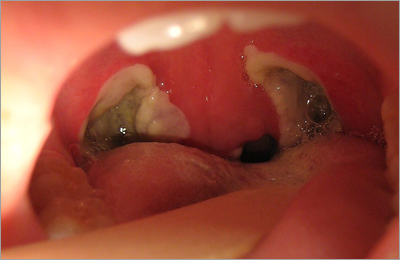

He has special interest in endoscopic sinus surgeries, microscopic surgeries and thyroid surgeries.